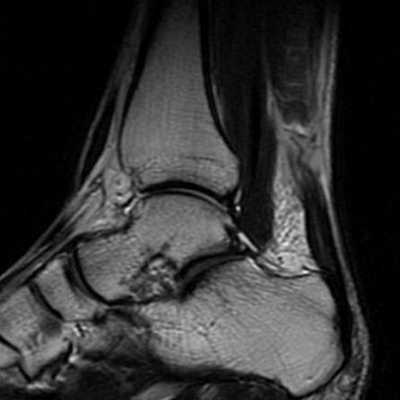

Помимо клинической картины важно и инструментальное обследование. Для планирования оперативного вмешательство наиболее актуально использование МРТ. Благодаря МРТ можно не только получить инструментальное подтверждение диагноза, но также оценить размеры дефекта, степень дегенеративных изменений свободного конца сухожилия, запланировать уровень резекции пяточной кости и предположительную удалённость зоны удлиняющей сухожилие пластики.

При МРТ исследовании определяется обширная зона дегенерации сухожилия, значительно превышающая размер дефекта.

После сбора анамнеза с указанием типичного механизма травмы приступаем к осмотру. Помимо отёка и кровоподтёка важным диагностическим критерием является угол который расслабленная стопа принимает в положении сгибания в коленном суставе до 90 ° по сравнению со здоровой стороной. В норме этот угол составляет 15-25° и он одинаков с обеих сторон.

При пальпации часто удаётся обнаружить дефект, увеличивающийся при тыльном сгибании стопы.